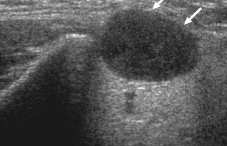

This nodule within the right lobe of the thyroid most likely represents:

Follicular adenoma

Which ultrasound finding is most characteristic of a follicular adenoma?

Hypoechoic peripheral halo caused by a complete fibrous capsule